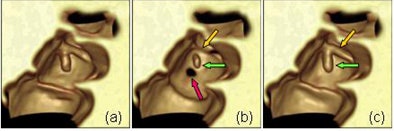

| Illustration of the artifact of degradation of the soft-tissue structures in electronic cleansing method. A thin haustral fold [arrow in (a)] submerged in the tagged materials was erroneously removed after the application of a thresholding-based electronic cleansing method [arrow in (b)]. A small polyp [arrow in (c)] submerged in the tagged materials was erroneously removed by the electronic cleansing method [arrow in (d)]. |

"A second kind of artifact is a false fistula caused by similarity between the lumen tagging boundary and the tagged tissue air layer," he said, wherein the similarity in attenuation values at this interface can produce pseudo polyps and folds due to partial volume effects. "When electronic subtraction is applied you see some kind of false fistula," Yoshida said.

| Illustration of the artifact of false fistula in electronic cleansing. The thin haustral folds sandwiched by the tagged regions and the lumen, called tagging-tissue-air layers (orange arrows, left image), are erroneously removed as the boundaries between lumen and tagged materials (such as the ones indicated by the green arrows), creating false fistulae as indicated by the orange arrows on the right image. |